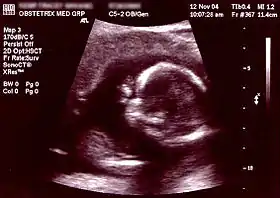

| Non-invasive | Ultrasound detection | Commonly dating scans (sometimes known as booking scans or dating ultrasounds) from 7 weeks to confirm pregnancy dates and look for multiple pregnancies. The specialised nuchal scan at 11–13 weeks may be used to identify higher risks of Downs syndrome. Later morphology scans, also called anatomy ultrasound, from 18 weeks may check for any abnormal development. Additional ultrasounds may be performed if there are any other problems with the pregnancy, or if the pregnancy is post-due. | First or second trimester |

At early presentation of pregnancy at around 6 weeks, early dating ultrasound scan may be offered to help confirm the gestational age of the embryo and check for a single or twin pregnancy, but such a scan is unable to detect common abnormalities. Details of prenatal screening and testing options may be provided.

The anomaly scan is performed between 18 and 22 weeks of gestational age. The International Society of Ultrasound in Obstetrics and Gynecology (ISUOG) recommends that this ultrasound is performed as a matter of routine prenatal care, to measure the fetus so that growth abnormalities can be recognized quickly later in pregnancy, and to assess for congenital malformations and multiple pregnancies (i.e. twins).[27] The scan can detect anencephaly, open spina bifida, cleft lip, diaphragmatic hernia, gastroschisis, omphalocele, congenital heart defect, bilateral renal agenesis, osteochondrodysplasia, Edwards syndrome, and Patau syndrome.[28]